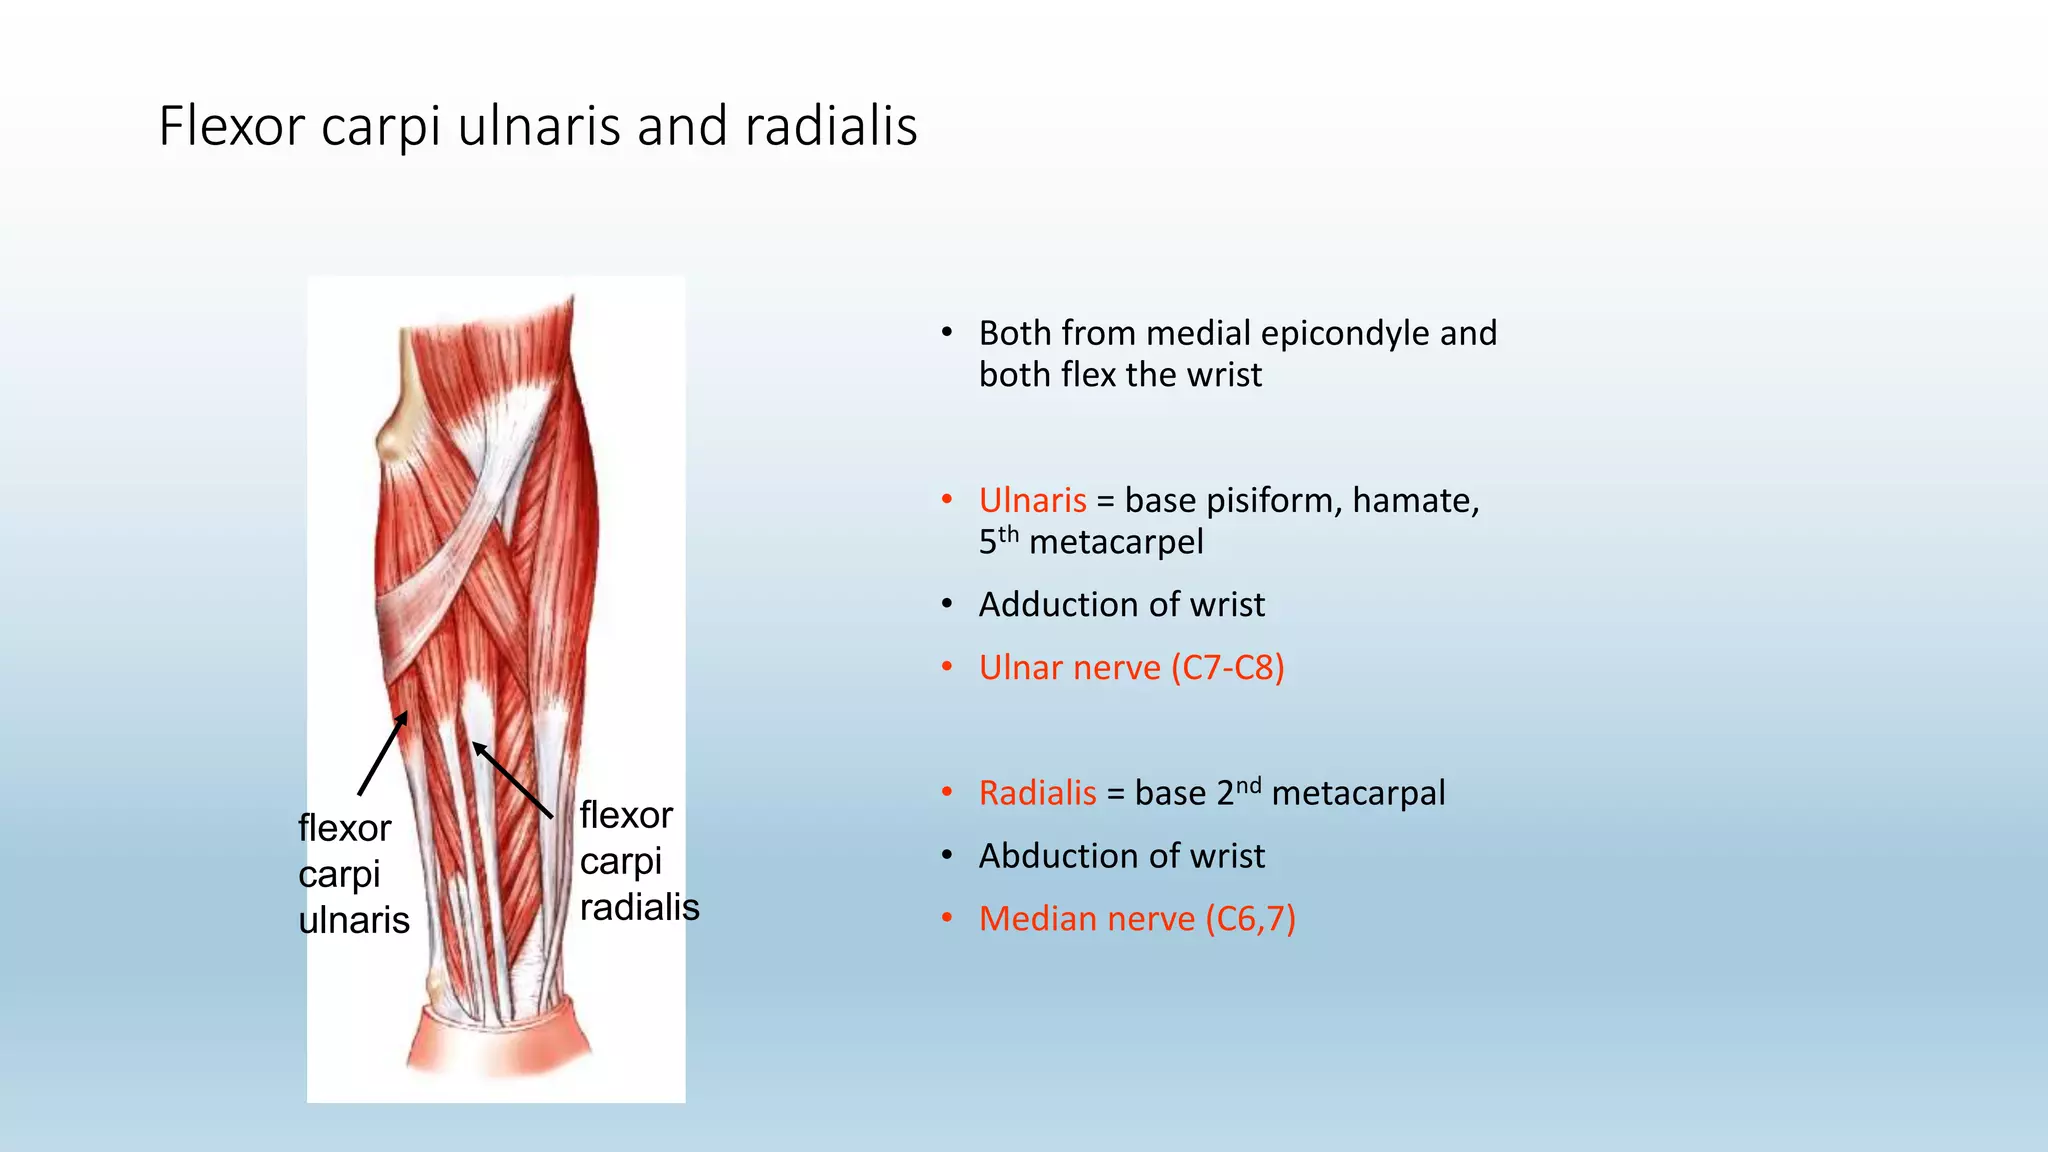

The document summarizes an anatomy revision session on the upper limb. It discusses various muscles of the upper limb including their origins, insertions, innervations and functions. Key muscles covered include the pectoralis major and minor, serratus anterior, deltoid, biceps brachii, brachialis, coracobrachialis, and triceps. It also discusses the rotator cuff muscles and muscles of the forearm including flexor carpi ulnaris and radialis. The session aims to help students identify upper limb muscles and understand their relations to nerves.